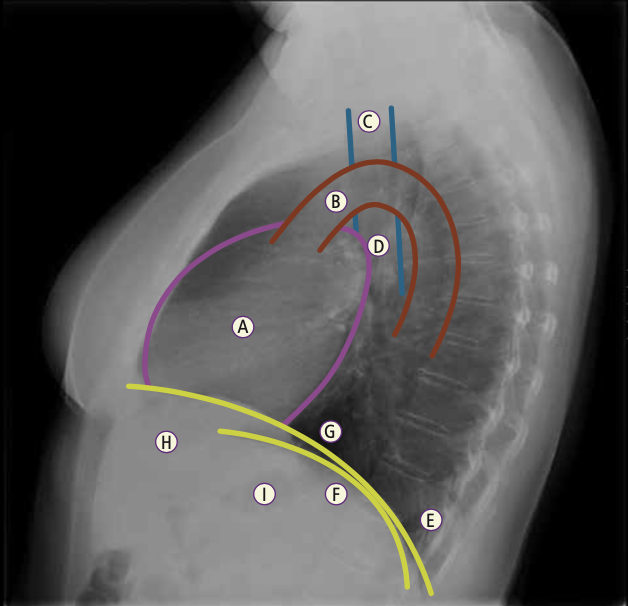

Observa y nombra la silueta de las diferentes estructuras que forman el mediastino en radiografía lateral.

Mediastino en radiografía lateral.

A: Corazón. B: Cayado aórtico. C: Tráquea. D: Hilio. E: Ángulo costofrénico. F: Diafragma izquierdo. G: Diafragma derecho. H: Hígado. I: Burbuja gástrica.